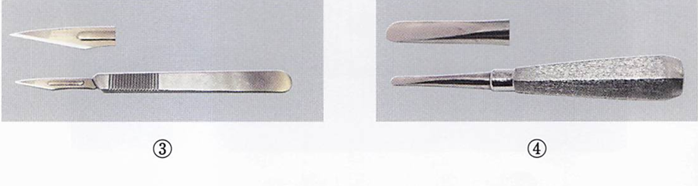

器具の写真を別に示す。 歯肉切除術に使用するのはどれか。2つ選べ。

a. ①

b. ②

c. ③

d. ④

解答を見る

a.d